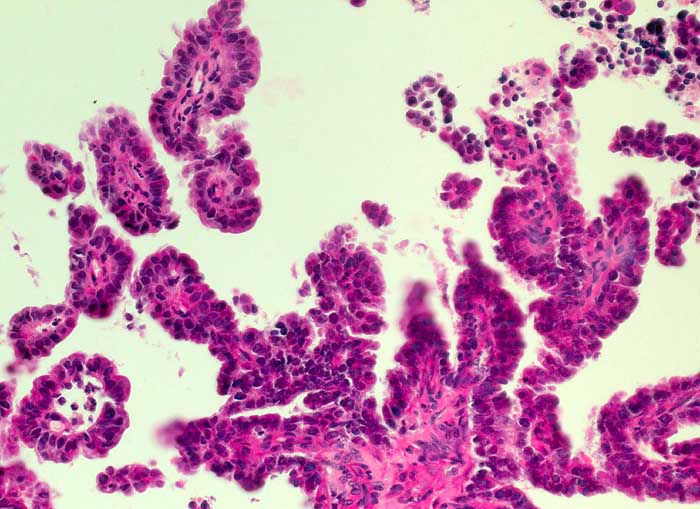

g/ Seröses Adenokarzinom des Endometrium

Seröses Adenokarzinom des Endometrium

Die Zellkerne der serösen Adenokarzinome sind in den meisten Fällen hochgradig atypisch. Das Zellbild gleicht entsprechend demjenigen eines wenig differenzierten endometrioiden Adenokarzinoms. Da das seröse Karzinom anders als das endometrioide Karzinom nicht Folge eines Hyperöstrogenismus ist, zeigen die meist postmenopausalen Patientinnen keinen hohen Aufbau des Vaginalepithels im PC-Abstrich.